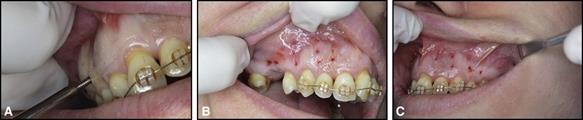

Fig. 3. Microperforaciones realizadas con la inserción y recuperación repetidas de A, mini tornillos en los lados B, derecho y C, izquierdo del maxilar. Este enfoque requiere el uso de más de 1 mini tornillo porque la cabeza pierde su borde después de varias penetraciones.

Técnicas para un tratamiento más rápido: decorticación (Wildondoncia y microperforaciones) y microvibraciones. La “ortodoncia osteogénica acelerada” a través de cortes corticales quirúrgicos interproximales (decorticación) no es más que otra aplicación del fenómeno acelerador regional, que produce resultados más rápidos que un tratamiento similar regular, independientemente del acuerdo con el plan de tratamiento, la perfección del acabado o el posibilidad de recesión periodontal.18 La microperforación adjunta (Park, Kang y Kim; 2006; Alikhani et al. 2013), se presentó como una alternativa viable para renunciar a la "agresividad" de las decorticaciones, con el objetivo de generar un movimiento dental mejorado por inflamación (Alikhani et al. 2013).

Los estudios iniciales en animales y humanos demostraron el potencial del método para promover un movimiento más rápido, pero quedan varias preguntas con respecto a la frecuencia de las microperforaciones (con qué frecuencia deberían repetirse) y el número de microperforaciones (cuántas veces deberían repetirse). y si la tasa es variable en diferentes pacientes). A nivel práctico, se encuentran disponibles kits comerciales de microperforación que permiten al ortodoncista "marcar" la profundidad de la microperforación (p. Ej., 2-3 mm). Este método también se puede aplicar a través de la inserción y extracción repetidas de mini tornillos de ortodoncia (Fig. 3).